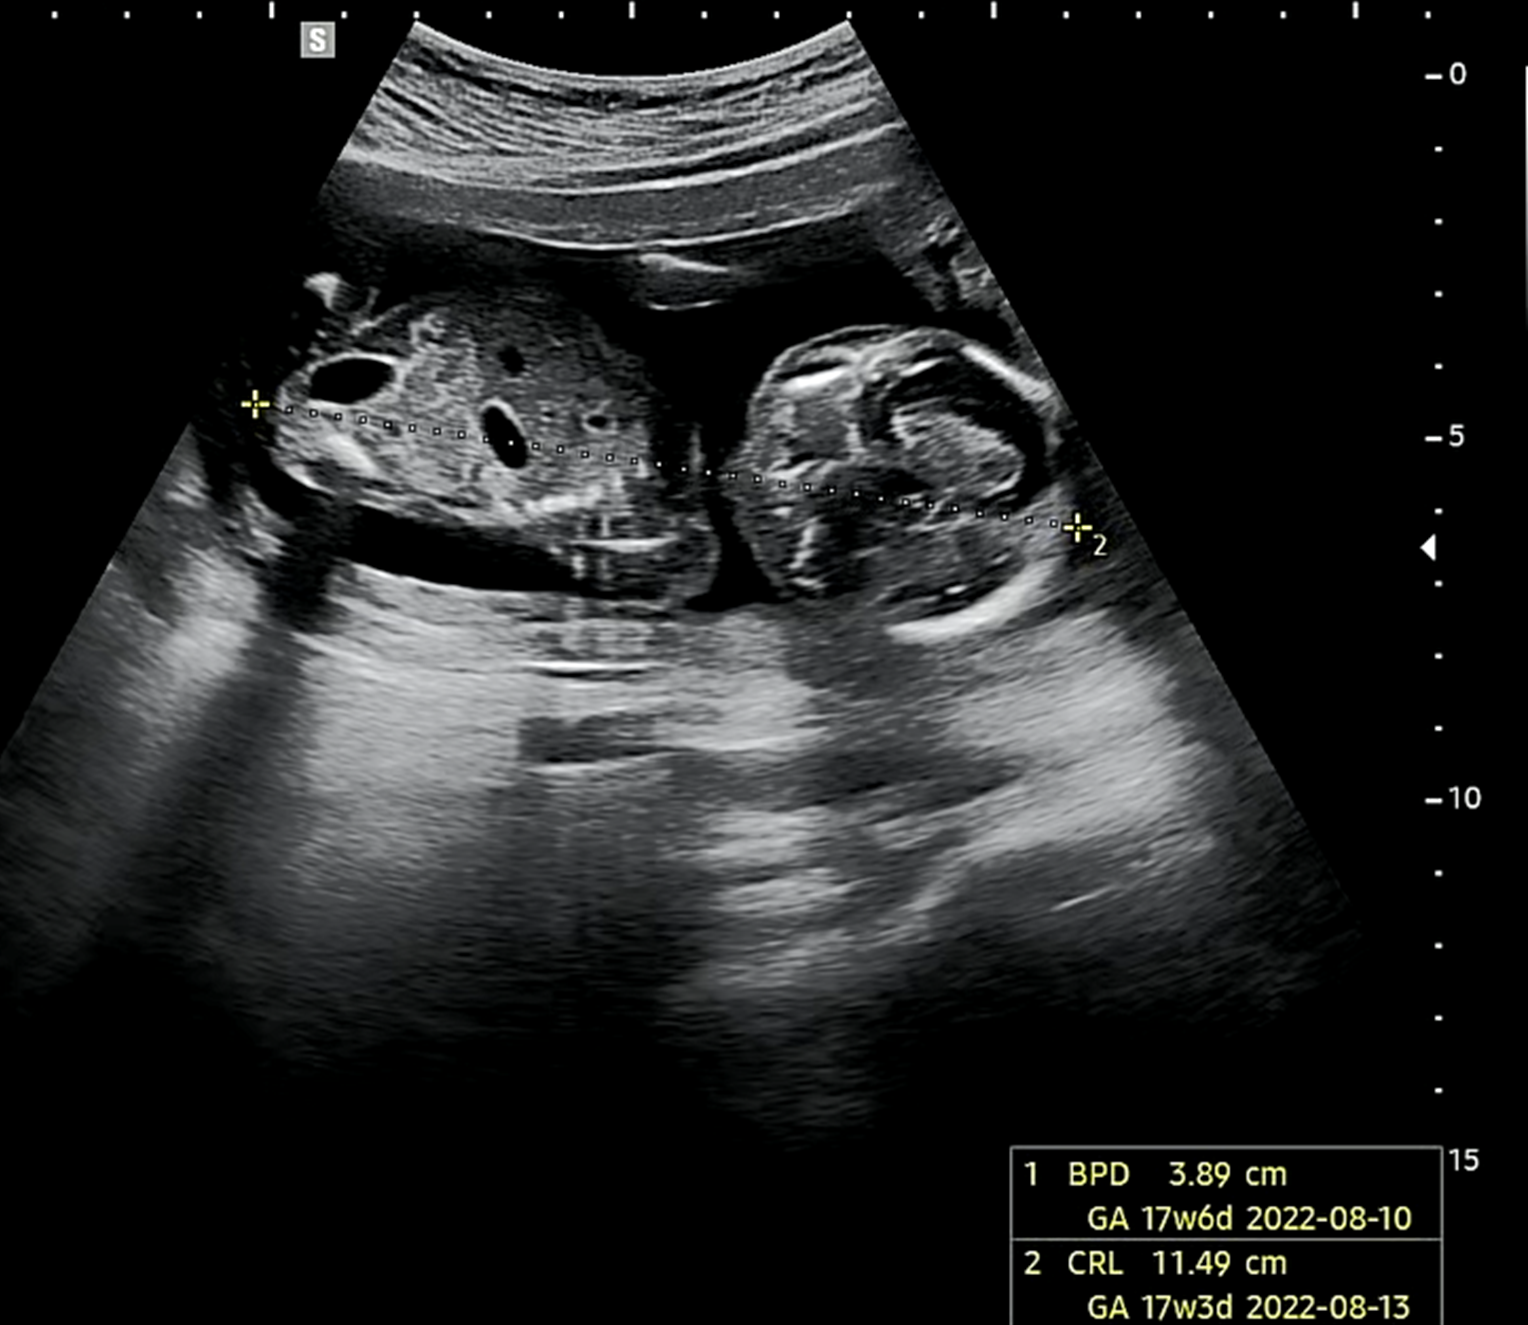

호띵이 머리 크기 (16주 차 3일) → 성장 상태 17주 6일

BPD : 태아의 머리 지름을 잰 수치로 임신 주수와 예정일 등 발달 속도를 추정

위의 표를 보면 16주에 적당한 머리크기는 32mm 정도이다. 호띵이가 38.9mm로 17주 6일 차에 적당한 크기로 1주 정도 성장이 빠르게 진행하고 있음을 확인하였다. 출산 시 머리 크기가 100mm를 넘어가면 자연분만이 어렵다고 하는데 호띵엄마 안 힘들게 적당히 크기를 바란다. 그래도 의사 선생님이 태반도 괜찮고 호띵이가 건강하게 잘 크고 있다고 하셔서 기분이 좋았다.

호띵이 키 → 성장상태 17주 3일

호띵이의 키는 17주 3일 차의 크기라고 한다. 16주 3일 차에 맞이한 지금보다 1주 정도 빠르게 자라고 있는 호띵이. 세상에 빨리 나오고 싶어서 무럭무럭 자라고 있는 것 같다.